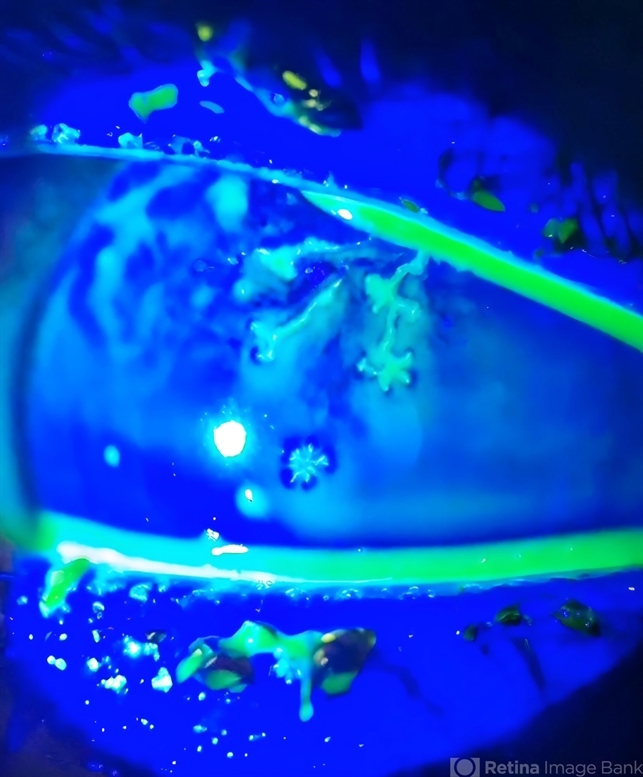

- dendritic keratitis, Herpes zoster, staining, Herpes simplex infection, herpes dendrite, corneal ulcer

- Slit lamp photograph of 32 year old male presented with herpetic corneal ulcer on staining with fluorescein dye under cobalt blue filted dendrits can be seen.